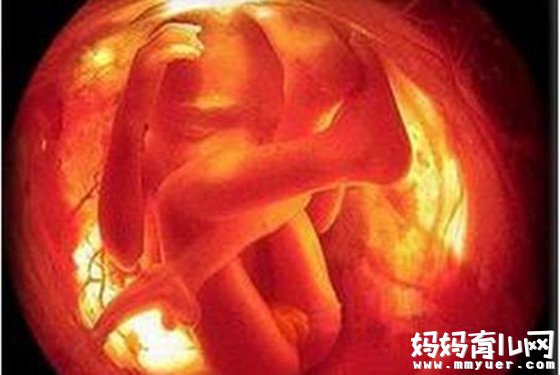

四维彩超可立体显示胎儿的颜色、面、各器官的发育情况,甚至胎儿在母体里的状态也可以观察到;对胎儿畸形,如唇裂、腭裂、骨骼发育异常、心血管畸形等能早期诊断。

了解胎儿宫内动态的一个胎动过程,再者动态摄录胎儿宫内资态,可以让孕妈妈看到胎儿一连串的动作,所以四维看起来会更清楚明了,还可以留作永久的纪念。

四维彩超,不仅可以感觉宝宝的呼吸和运动,而是可以亲眼目睹他们的一颦一笑和乖巧的状态。更为重要的是,四维彩超能够多方位、多角度